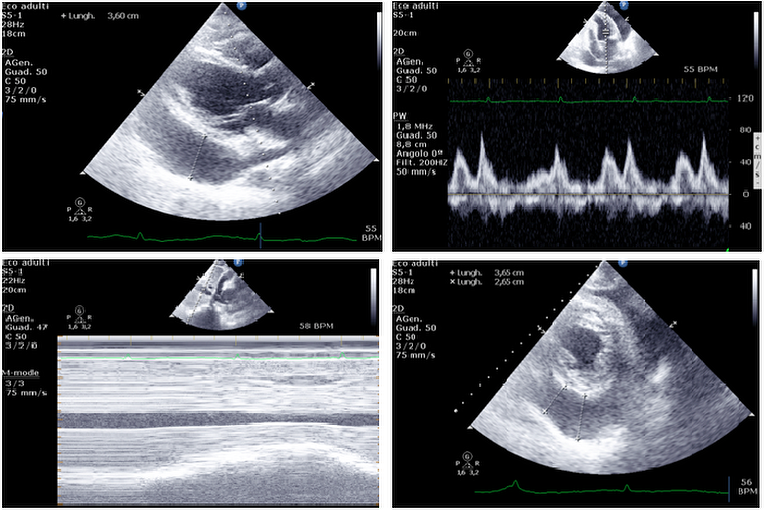

Pericardial effusion ("fluid around the heart") is an abnormal accumulation of fluid in the pericardial cavity. Because of the limited amount of space in the pericardial cavity, fluid accumulation leads to an increased intrapericardial pressure which can negatively affect heart function. ... Read Article

Large Hemorrhagic Pericardial effusion

Large hemorrhagic pericardial effusion. methods: We reviewed seven cases of large hemorrhagic pericardial effusions hospitalized in Soroka university Med- myocardial infarction, idiopathic, uremic, aortic dissection, and trauma [6,7]. ... Retrieve Here

MI,pericardial effusion With Thrombus: Free Wall Rupture ...

It is often difficult to have direct visualisation of free wall rupture by echo in myocardial infarction ,pericardial effusion(especially more than 10mm and with thrombus)is very helpfull indirect signe for diagnosis ... View Video